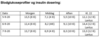

En 19-årig kvinde behandles for paracetamolforgiftning. Hun havde taget 50 tabletter et døgn før, hun blev bragt til akutmodtagelsen. Korrekt behandling blev straks iværksat. Blodprøver efter 12 og 36 timers behandling ses i skemaet. Hun virker somatisk upåvirket.

Hvordan skal disse resultater vurderes?

a. God effekt af behandlingen, fordi ALAT falder, og den skal blot fortsættes.

b. Hun tåler ikke N-acetylcystein, som har medført akut pancreatitis. Anden behandling skal iværksættes.

c. N-acetylcystein skal fortsættes, men med nedsat dosis på grund af nyrepåvirkning.

d. Hun har progredierende akut leversvigt og skal konfereres med Rigshospitalet om overflytning til observation mhp transplantation.

e. Hun skal fortsætte med N-acetylcystein, men behandlingen skal suppleres med K-vitamin, fordi stigende bilirubin og INR tyder på cholestase.

En 19-årig kvinde behandles for paracetamolforgiftning. Hun havde taget 50 tabletter et døgn før, hun blev bragt til akutmodtagelsen. Korrekt behandling blev straks iværksat. Blodprøver efter 12 og 36 timers behandling ses i skemaet. Hun virker somatisk upåvirket.

Hvordan skal disse resultater vurderes?

a. God effekt af behandlingen, fordi ALAT falder, og den skal blot fortsættes.

b. Hun tåler ikke N-acetylcystein, som har medført akut pancreatitis. Anden behandling skal iværksættes.

c. N-acetylcystein skal fortsættes, men med nedsat dosis på grund af nyrepåvirkning.

d. Hun har progredierende akut leversvigt og skal konfereres med Rigshospitalet om overflytning til observation mhp transplantation.

e. Hun skal fortsætte med N-acetylcystein, men behandlingen skal suppleres med K-vitamin, fordi stigende bilirubin og INR tyder på cholestase.